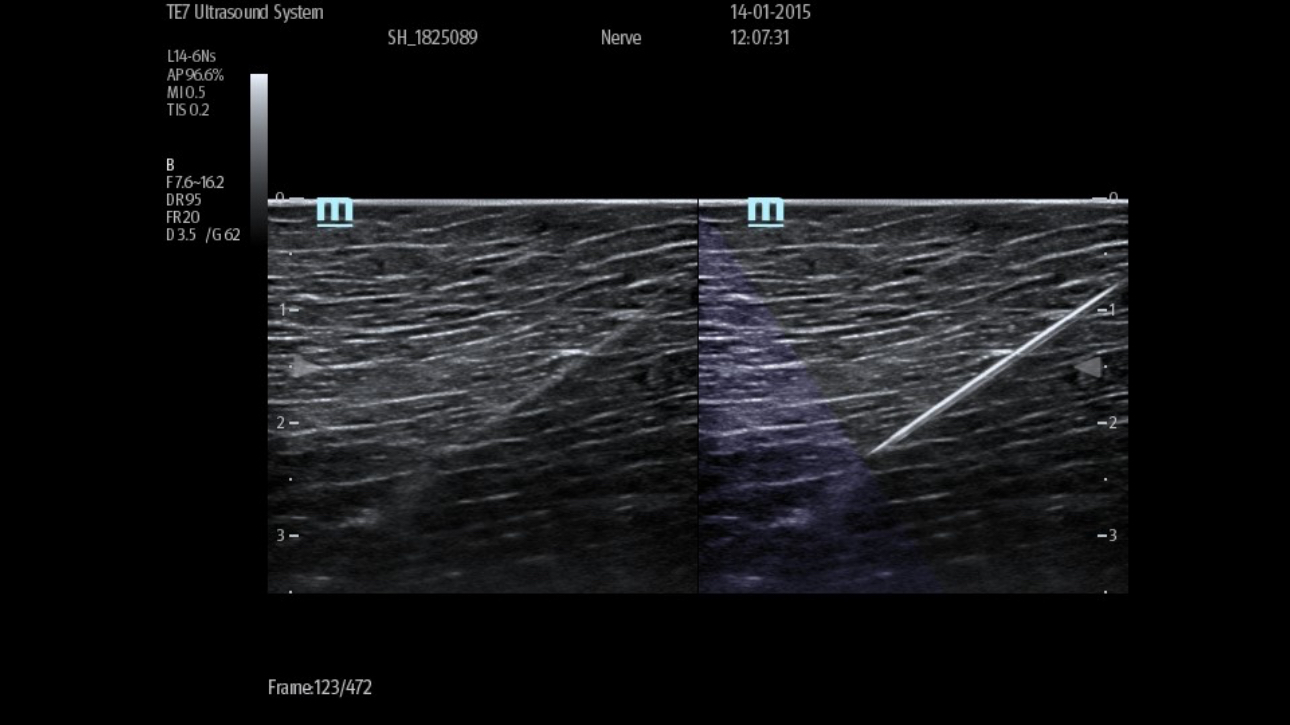

eSpacial Navi??and iNeedle+TM?ensure safe needling solution. Up to 20MHz ultra-high frequency linear transducer can visualize the finest nerves and fibers with extremely high resolution. Seamless monitor with full touch screen and exclusive clean-lock function ensure efficient cleaning and disinfection. The multiple modality design enables the TE5 to easily handle a wide range of medical scenarios.